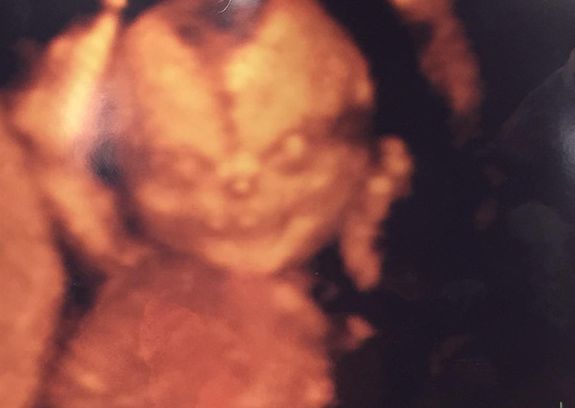

Um casal decidiu compartilhar os resultados de seu ultra-som 4D, um determinado tipo de teste que usa ondas sonoras para produzir uma imagem do bebê de dentro do ventre, quanto notaram algo muito peculiar.

“[Minha] esposa e eu fomos pegar o ultra-som do nosso filho e esta imagem mudou nossas mentes”, disse o homem que não quis se identificar.